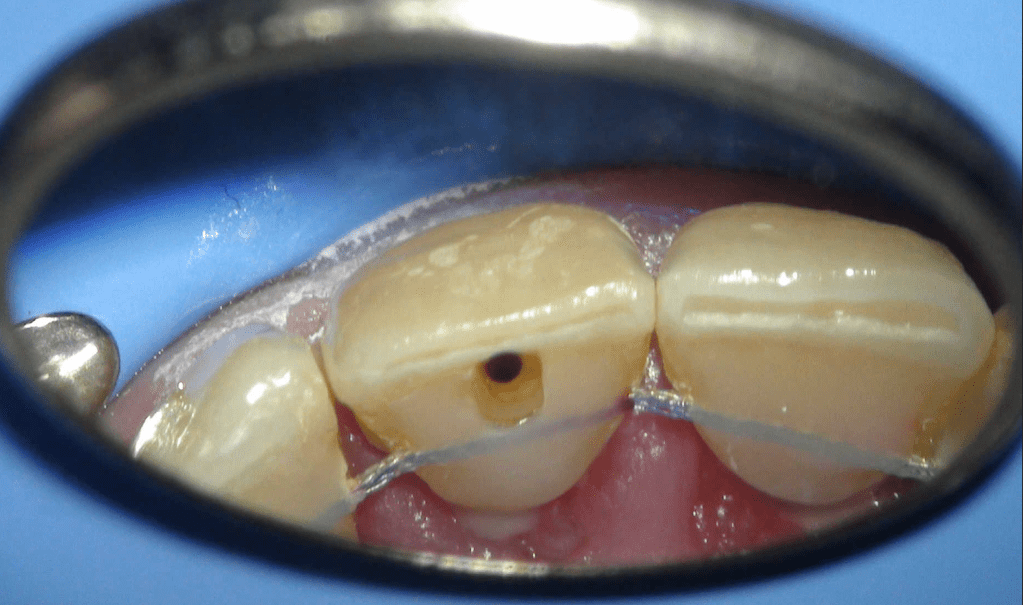

Acceso ultraconservador a través de incrustación reciente